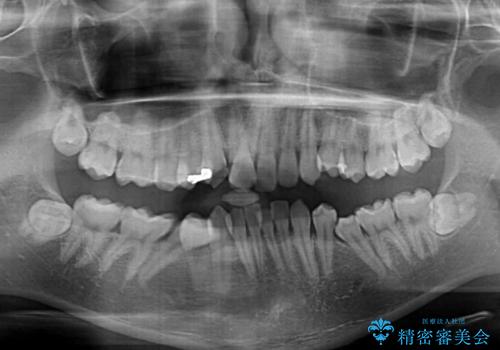

叢生が強く、歯が並ぶスペースが不足していたため、

上下左右の第一小臼歯を抜歯して、矯正治療のための適切なスペースを確保する計画としました。

上顎左側第一大臼歯に齲蝕が認められたため、矯正治療終了後に 精度の高いセラミックインレー にて修復治療を行いました。